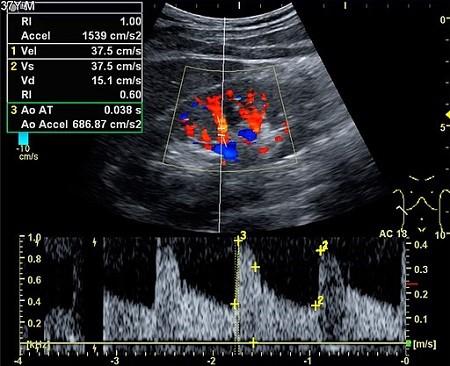

The sound waves may also be converted to colour pictures on a screen so that flow can be seen through the arteries or veins (colour Doppler) - as below.

Colour Doppler ultrasonography

By Mikael Häggström [CC0] (Own work), via Wikimedia Commons

They may also be plotted on a graph showing changes in speed and direction (velocity).

Duplex ultrasound is a special technique which combines traditional ultrasound with Doppler ultrasound. Images of the solid object being examined - for example, the artery and the blood flowing through it - are displayed on a screen or monitor.

The object is usually grey and the blood flow is usually in colour (colour Doppler).

The images below are produced from a Doppler scan of the kidney.

Kidney ultrasound scan

By Kristoffer Lindskov Hansen, Michael Bachmann Nielsen and Caroline Ewertsen [CC BY 4.0 (https://creativecommons.org/licenses/by/4.0)], via Wikimedia Commons